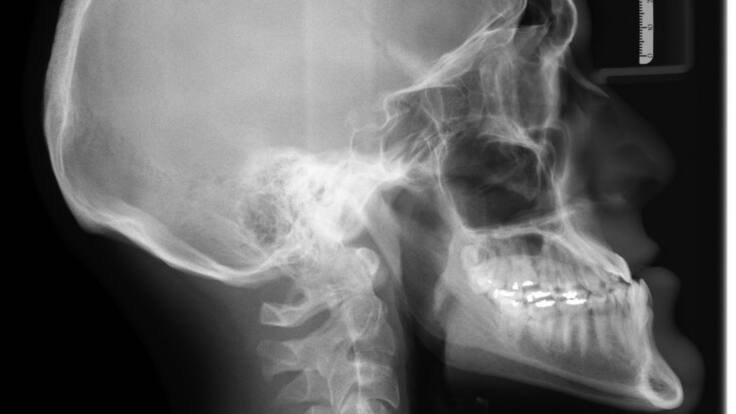

¿Cómo evitar enfermedades relacionadas con los huesos?

La exposición al sol, una alimentación adecuada y el ejercicio, son características que ayudan a la formación de los huesos y su excelente estado.

Escuche el audio del 02 de junio con José Durazo, Médico Ortopedista y traumatólogo, hablando sobre el Cuidado de los huesos.